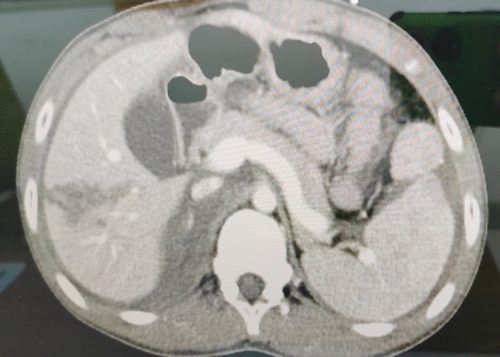

胸腹部增強(qiáng)CT造影等檢查

胸心普通外科主任吳新宇

憑借豐富經(jīng)驗及檢查結(jié)果

診斷為

腹部閉合傷

肝破裂

失血性休克